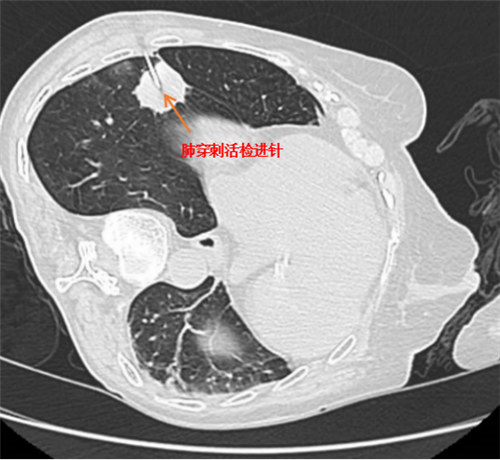

张海莲医师在评估患者病情后,与家属沟通并取得同意,为患者实施了 CT 引导下肺穿刺活检术,成功获取了病变部位标本,并送检病理科病理学检查。